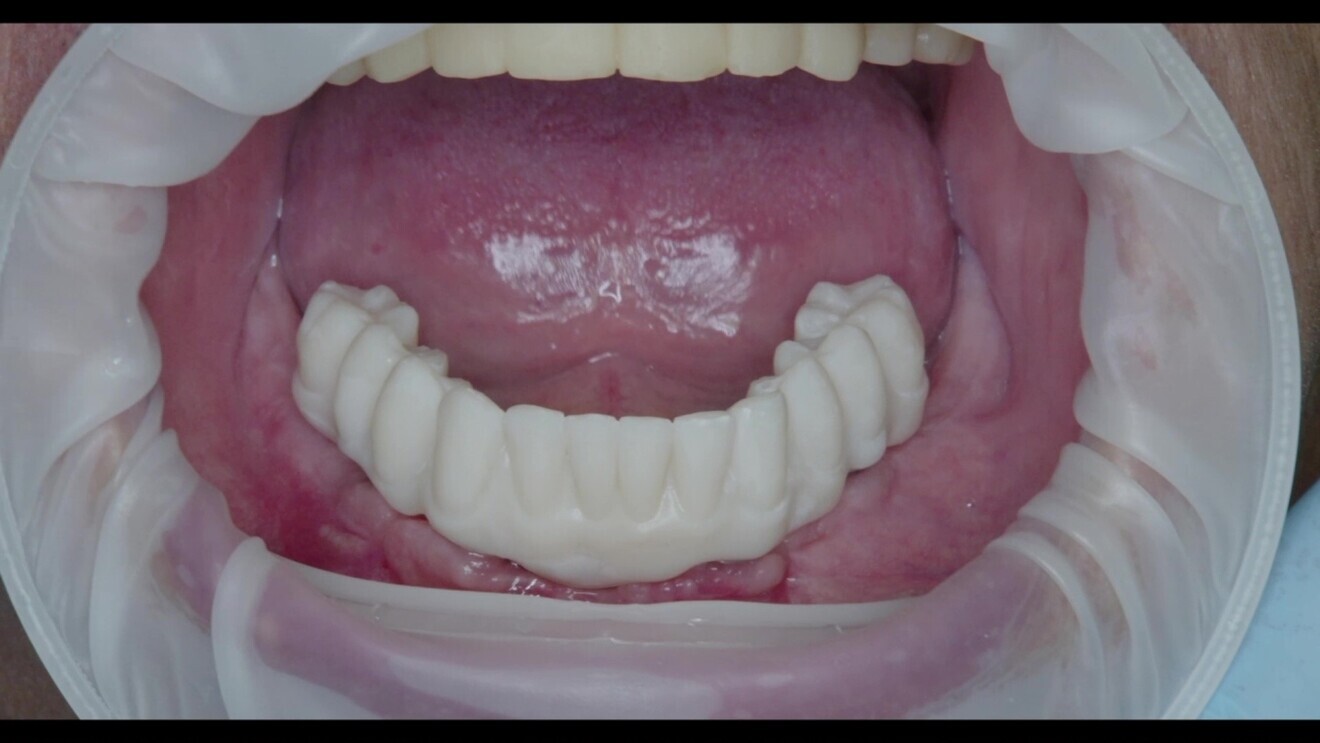

Fig. 14: Try-in of the lower jaw prosthesis.

In this case, the final prostheses were fabricated using monolithic KATANA Zirconia YML (Kuraray Noritake Dental). This high-quality material offers excellent strength, durability and aesthetics for dental restorations. The staining process was performed using CERABIEN ZR FC Paste Stain (Kuraray Noritake Dental) to achieve a natural appearance and blend seamlessly with the patient’s existing dentition. PANAVIA V5 in the shade Opaque and CLEARFIL CERAMIC PRIMER PLUS (both Kuraray Noritake Dental) were used to cement the bases (Elos Accurate Hybrid Base H Non-Engaging compatible with Straumann Standard and Standard Plus 4.8 mm diameter, regular neck implants; Elos Medtech; Figs. 15–22).

Fig. 17: The nal prosthesis on the day of delivery.

Fig. 18: Final prostheses of monolithic KATANA Zirconia YML, stained using CERABIEN ZR FC Paste Stain. The dark gingiva spots were stained with the shade Red, the light pink surfaces with the shade Pink and the highlights with the shade Salmon Pink.